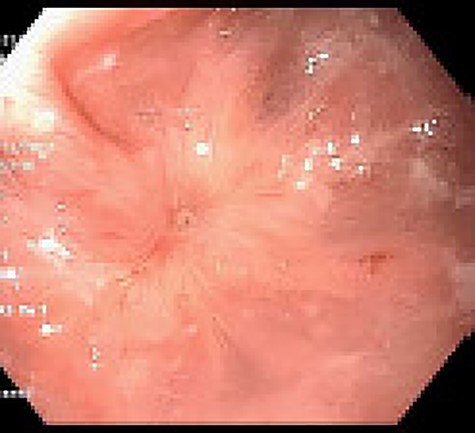

Approximately 2 months into his postoperative course, he returned with symptoms of dysphagia. esophagogastroduodenoscopy (EGD) revealed benign-appearing stenosis at the level of the esophagogastric anastomosis. This was initially dilated with a balloon. However, due to recurrent symptoms, a fully covered SEMS was placed to alleviate stricture (Figs 1, 2). The patient did well for nearly 2 months before returning with recurrent symptoms. A new web was visualized causing complete luminal obstruction (Fig. 3). This was unable to be traversed in antegrade fashion, requiring retrograde access via the jejunostomy utilizing guidewire. A pediatric colonoscope was able to be passed over the guidewire and dilate before subsequent SEMS deployment (Fig. 4). This stent was secured using 2-0 polypropylene suture via Overstitch device (Fig. 5). The initial SEMS was found to have migrated to the mid portion of the gastric conduit. However, due to the small caliber of the proximal stricture and to avoid disrupting newly deployed stent, the initial SEMS was left in place.